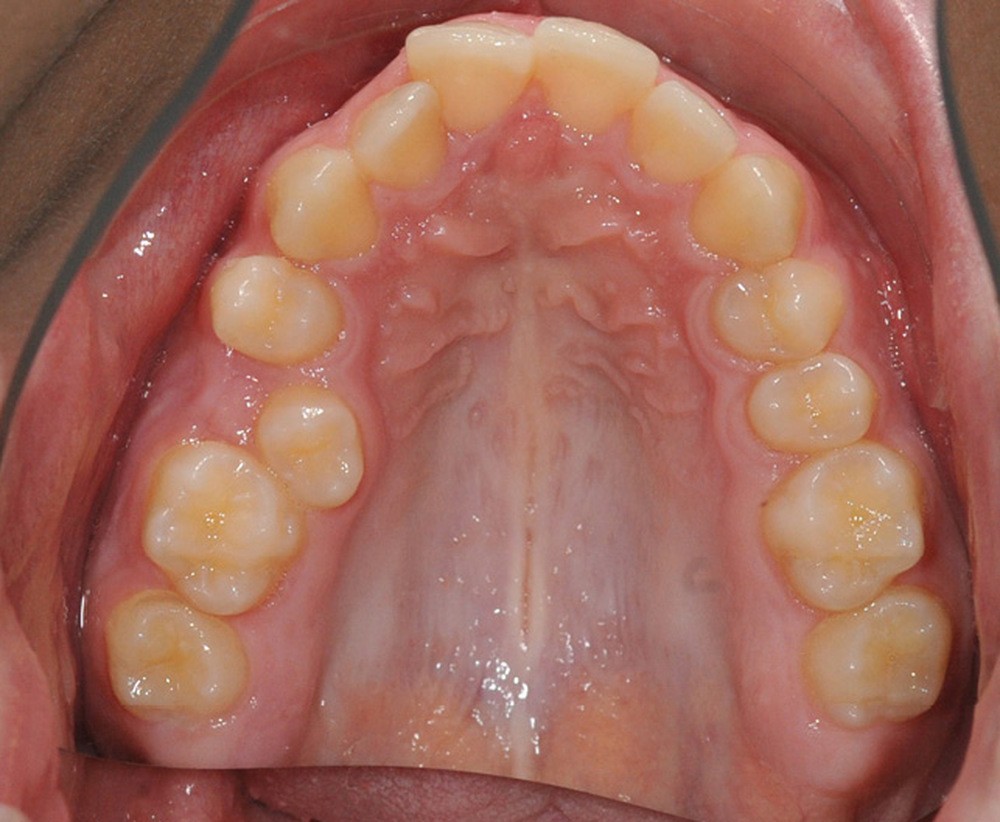

C’est à ces questions que nous permettront de répondre les deux premiers conférenciers, parodontologistes : le Dr Béatrice Straub nous présentera le renfort parodontal minéralisé, technique qu’elle a développée et pratique depuis de nombreuses années, pour éviter les préjudices des mouvements orthodontiques à risque, notamment lors des décompensations préchirurgicales (fig. 1a-d) ; le Pr Anton Sculean abordera le thème des greffes, avec leurs indications, les différentes techniques à privilégier et illustrera ses propos par de nombreux cas cliniques aux résultats esthétiques impressionnants.

La matinée s’achèvera par le traitement de la dysharmonie dent-arcade par des techniques chirurgicales originales et novatrices : l’expansion transversale maxillo-mandibulaire (Dr Jean-Luc Ouhioun, fig. 2a-h) et la distraction sagittale du bloc incisivo-canin « front-block de Triaca » (Dr Olivier Esnault).